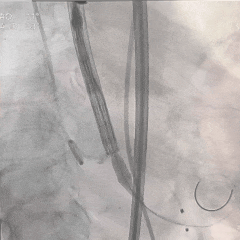

TF29瓣膜,0位初始定位

全展开造影,大弯侧位置尚可

左侧位造影,小弯侧位置偏深

回收后调整瓣膜释放位置

全展开造影,瓣膜位置较高

多体位造影,瓣膜位于瓣上

再次回收,第三次释放

全展开造影,大弯侧0位

左侧位造影,小弯侧深度可

脱钩后造影,瓣膜位置可

外周血管检查,无损伤